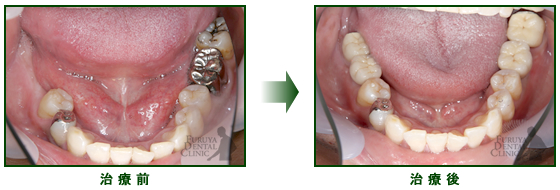

60代 男性

下の奥歯が入歯で安定悪く、咬みにくいそうです。奥歯にインプラントを入れて、全体にしっかり噛めるようになりました。